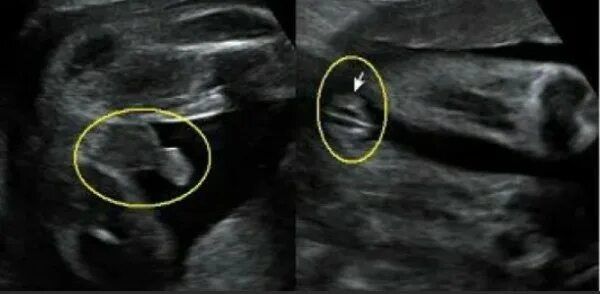

Нана, вот,это не моё,тут у девушки 24 недели и ей на этом узи тоже сказали ,что это девочка,потом она пошла на 3 скрининг,и все таки это мальчик, и родила мальчика. Изображение

07.12.2024